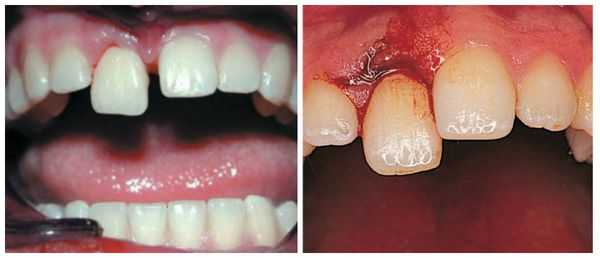

Симптомы вывиха зуба

- Неполный вывих : боль усиливается при контакте с зубом, например во время приёма пищи; на слизистой оболочке полости рта имеются маленькие ранки, ссадины и гематомы; мягкие ткани отёчны; наблюдается смещение зуба в сторону и его значительная подвижность; вынужденное положение челюсти в связи с наличием болевых ощущений.

- Полный вывих: сопровождается сильной болью; зуб в лунке отсутствует; пустая лунка кровоточит; десна изменена в цвете; имеется припухлость; может возникнуть гематома; происходит локальное повышение температуры; некоторое время могут наблюдаться дефекты речи.

Для всех видов вывиха характерна следующая симптоматика: боль в области причинного зуба, кровоточивость, отёчность десны.